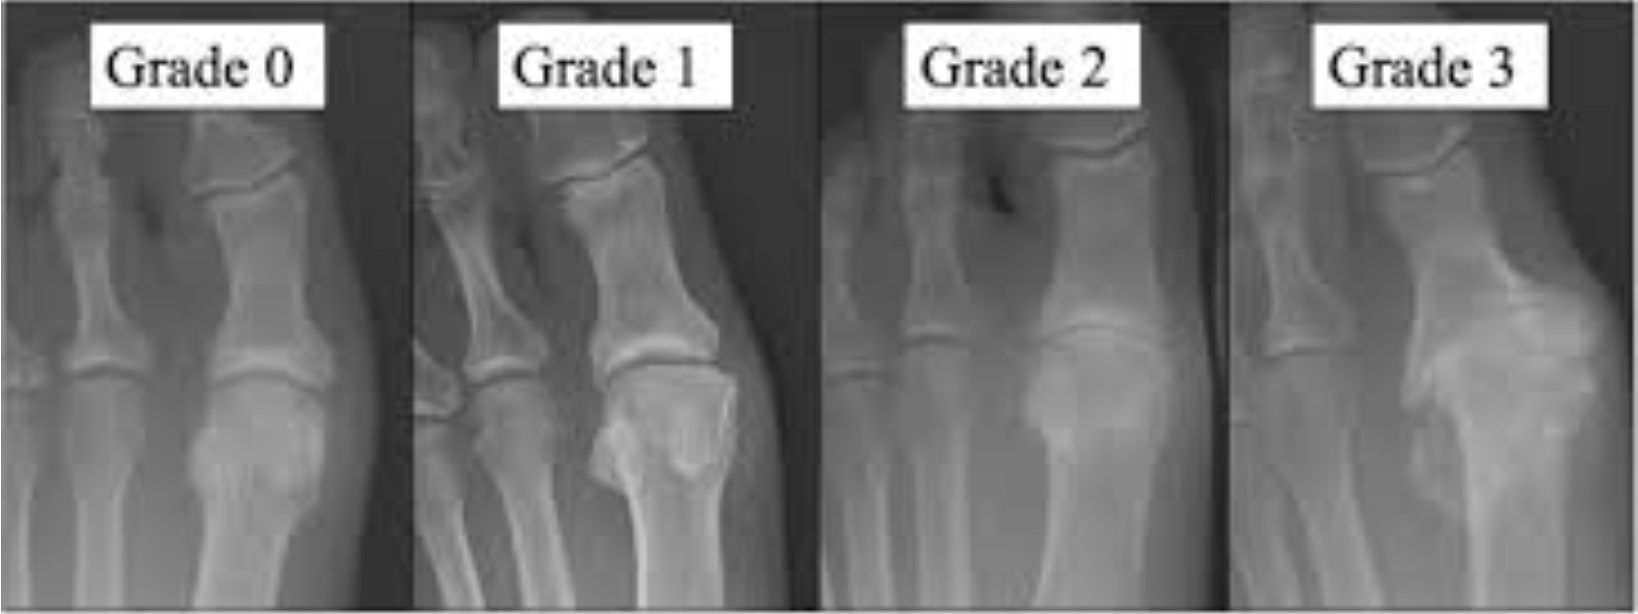

外反母趾